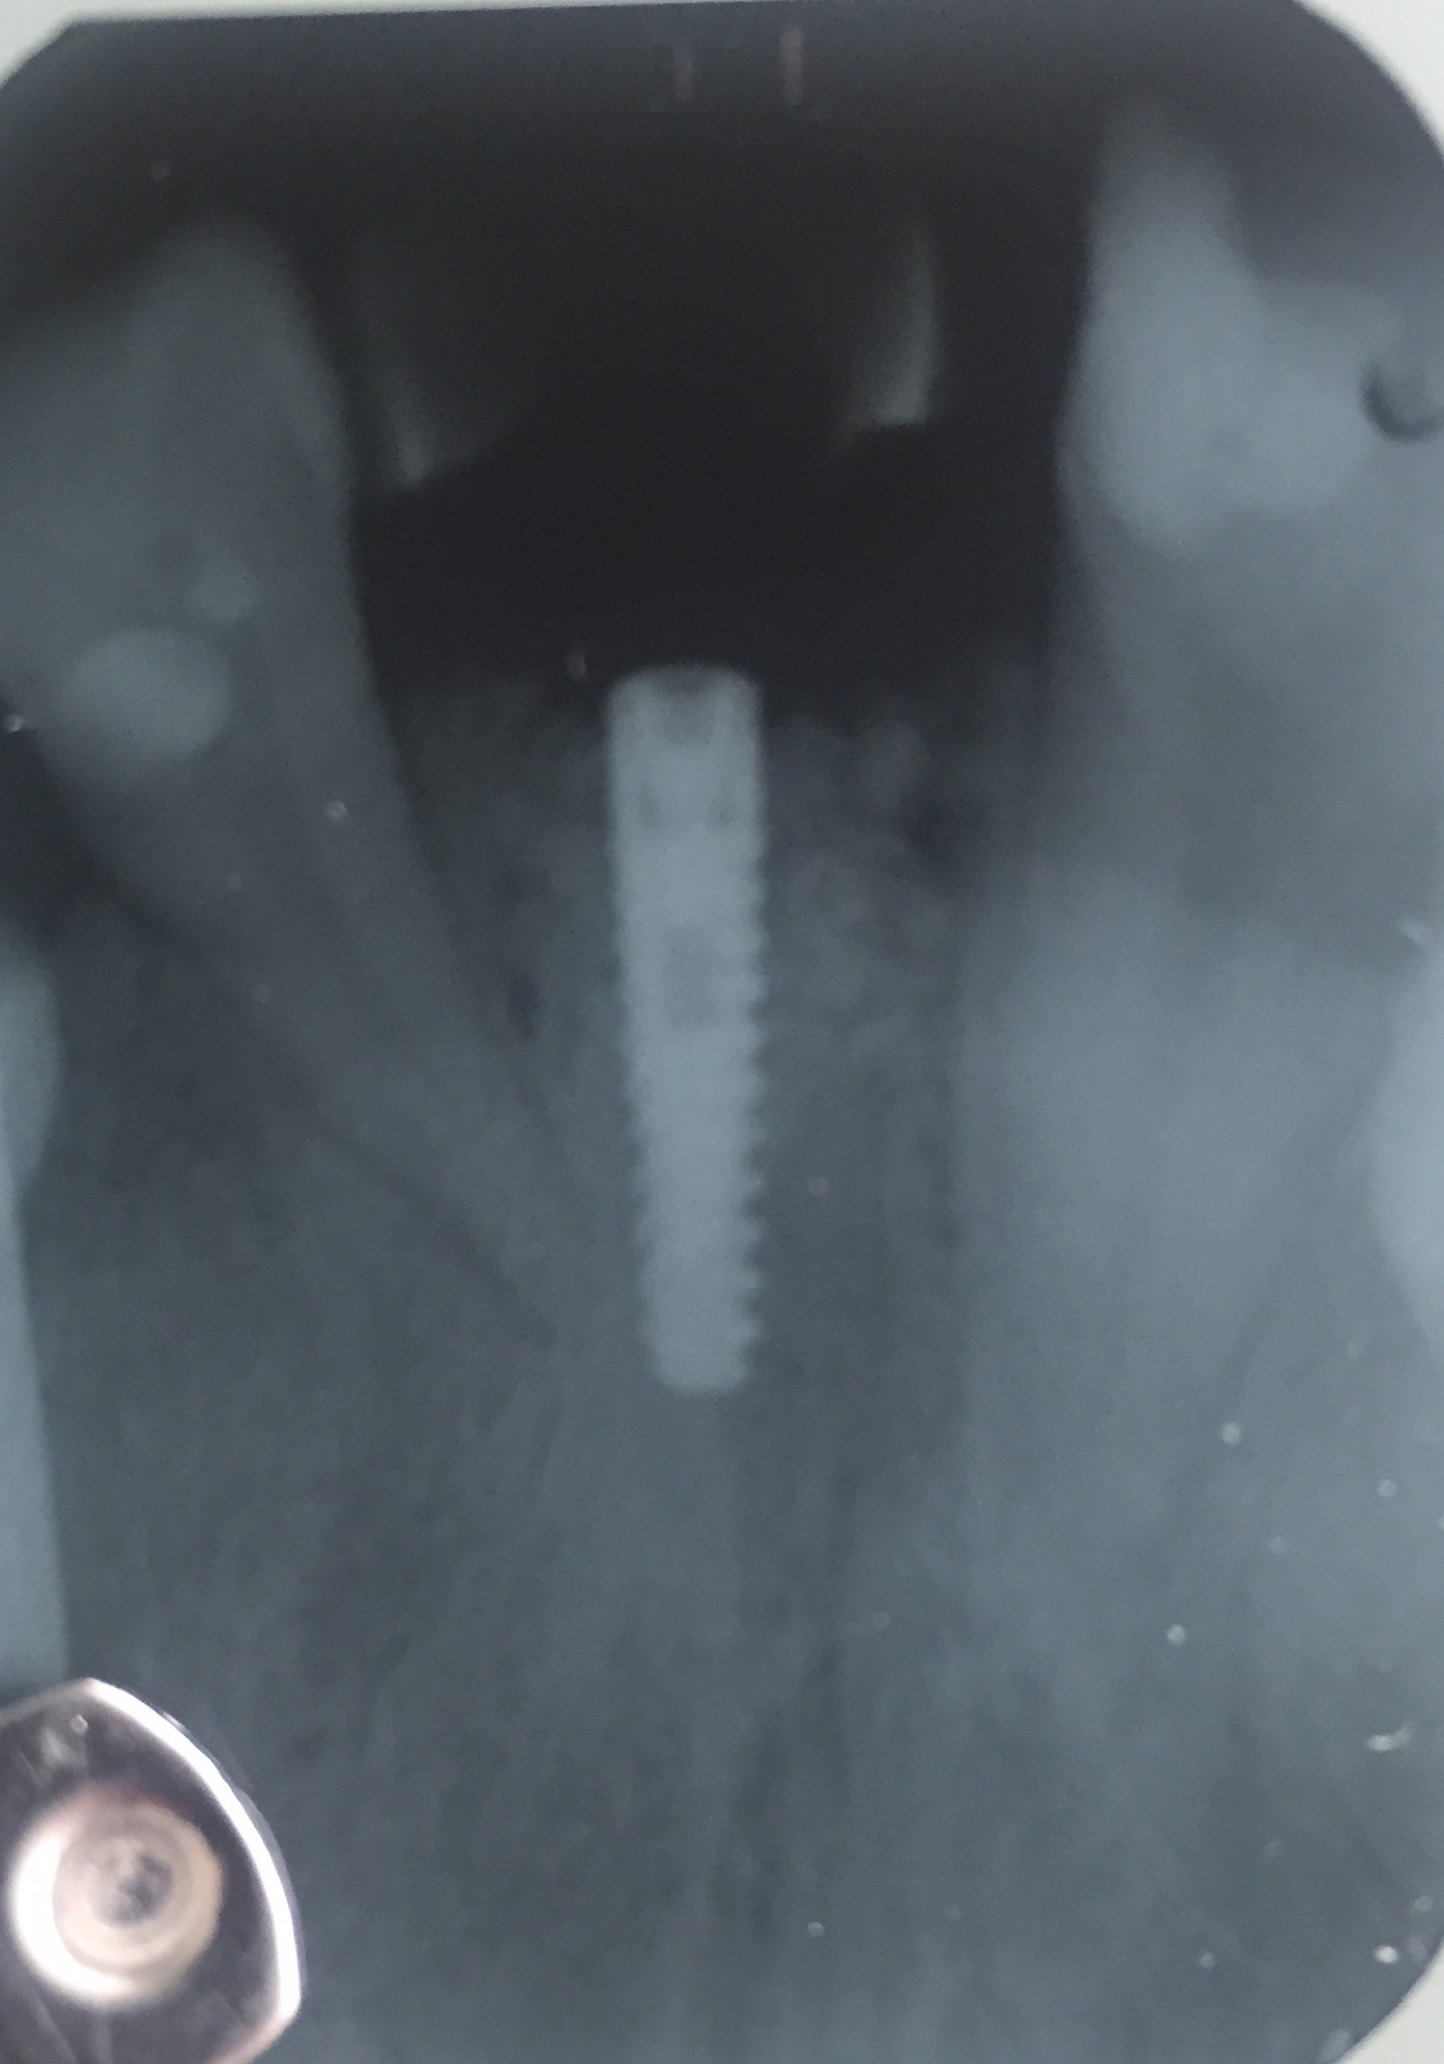

Buenas. Me gustaría saber qué marca de implante, conexion y tamaño. ccHe conseguido desatornillar Corina y poner pilar de cicatrizacion GRACIAS

buenas noches compañeros, este implante se lo colocaron a un chico hace 7-8 años y desde entonces va con el provisional, alguien podría ayudarme con la marca y el tipo [...]